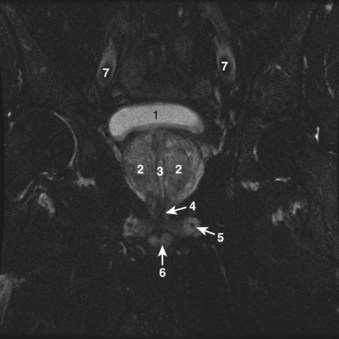

Figure 2–38 Axial T2-weighted magnetic resonance image of the male pelvis through the prostate gland and adjacent structures. 1, urinary bladder; 2, lateral lobes of prostate; 3, verumontanum; 4, striated urethral sphincter; 5, inferior pubic ramus; 6, corpus spongiosum in cross section; 7, external iliac artery.